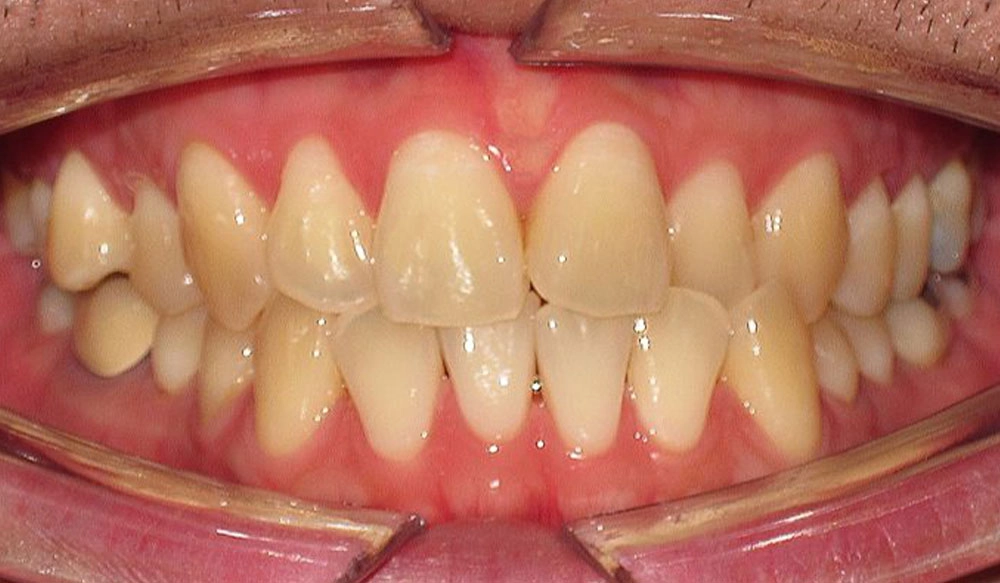

Crowding

Crowding is the condition in which there is a discrepancy between tooth size and space available for the teeth to be aligned in the dental arch

Patient Information:

Age: 17

Gender: female

Invisalign Treatment Option: Invisalign Comprehensive

Total Treatment Time:

29 months